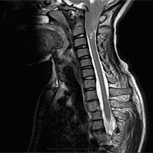

我們是一家位於西班牙巴塞隆納的國際專科醫療中心,不設分院,專注於精準且高品質的醫療照護。我們採用微創手術從病因治療Arnold-Chiari I型症候群、特發性脊髓空洞症與脊柱側彎等相關疾病,致力於為來自世界各地的患者帶來更安全、更有效的治療選擇。